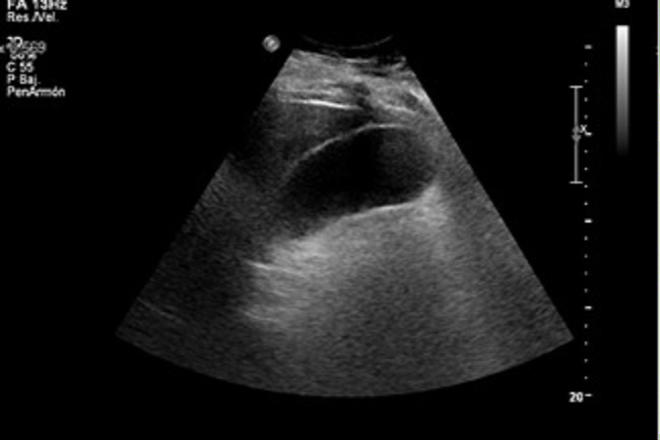

Correlación ecográfica-laparoscópica en colecistitis crónica y aguda

La litiasis vesicular es la patología más frecuente en este órgano y obviamente la  colecistectomía es la cirugía mas realizada, específicamente bajo la técnica laparoscópica, siendo la ecografía el estudio de mayor relevancia para evaluar las características anatómicas en su fase aguda o crónica y no solo por su sencillez, fácil acceso y bajo costo relativamente en comparación con otros estudios.

TIPO l: Lumen visible, pared delgada de ≤a 3 mm, cálculos visibles (colelitiasis o colecistitis crónica)

TIPO ll: Vesícula distendida, lumen visible, cálculos visibles y pared engrosada > a 3 mm y a su vez se dividieron en 2 grupos de acuerdo al grosor de la pared; IIA grosor de pared de ≤ 5 mm, IIB grosor de pared > 5 mm (colecistitis aguda litiásica)

TIPO III: Lumen no visible, pared de grosor indeterminado, uno o más cálculos son sombra acústica (vesícula esclerotrófica).